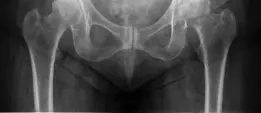

الأشعة السينية (X-rays)

هي الخطوة الأولى والأساسية في التشخيص. يتم أخذ صور أمامية خلفية (AP) للحوض والورك المصاب، وصور جانبية للورك.

* ماذا تظهر الأشعة السينية: تُظهر الأشعة السينية بوضوح خط الكسر وموقعه (داخل المحفظة المفصلية أم خارجها)، ودرجة التبادل (إزاحة العظام عن مكانها الطبيعي)، وقصر الساق إن وجد، وجودة العظم.

* في حالة المريض: أظهرت الأشعة السينية كسرًا متبدلًا في عنق الفخذ الأيسر، وكان خط الكسر داخل المحفظة. ظهر رأس الفخذ مزاحًا للأعلى والخلف.

الشكل 1: صورة أشعة سينية أمامية خلفية للحوض توضح كسر عنق الفخذ الأيسر المتبدل.